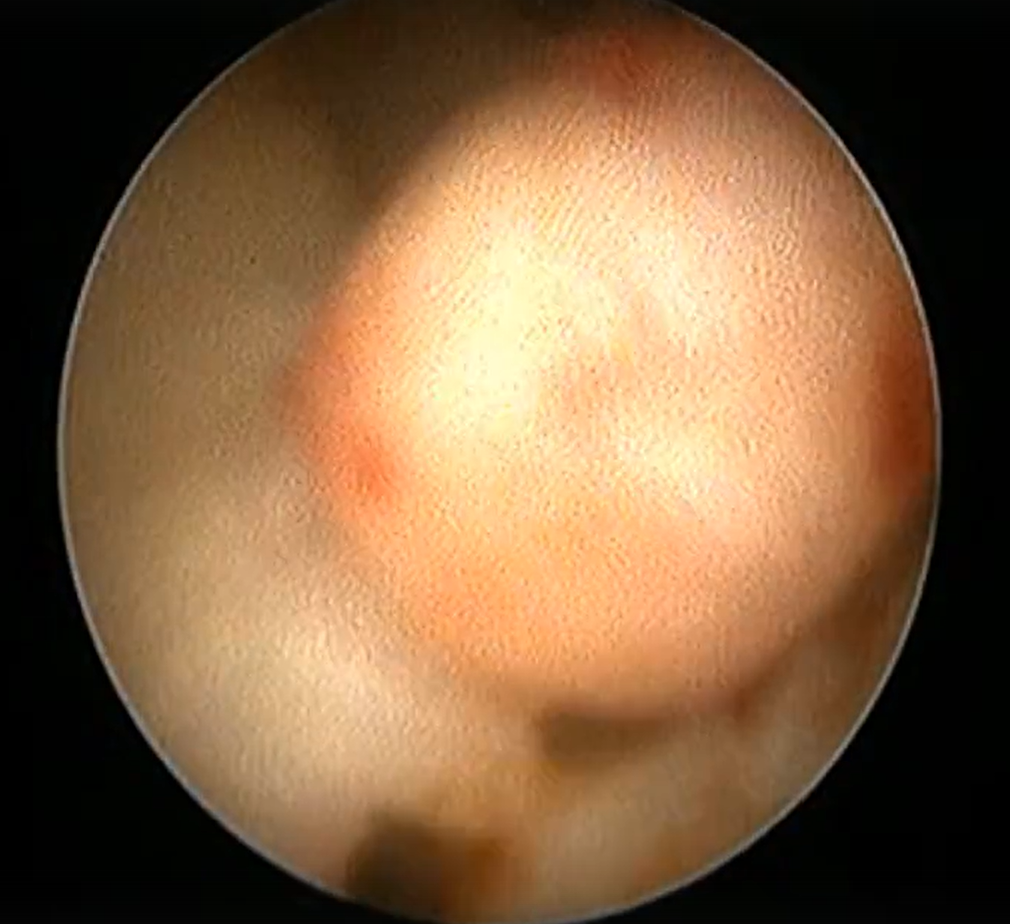

Устранение недержания мочи у самок методом TRUST. . . . Собака 14 лет. Метис. В первые годы жизни проведена полостная овариогистерэктомия (стерилизации). В течение последних лет наблюдается недержание мочи(гормонассоциированное). Проводимая терапия фенолпропаноламином, препараты давали положительный эффект на протяжении длительного времени (при этом постепенно повышалась доза и уменьшалась эффективность). Владельцы приняли решение о проведении малоинвазивной, чрезпросветной, эндоскопической операции (уретроцистоскопия) методом TRUST(патент Чернова А.В.) Подобная манипуляция позволяет разрешить проблему недержания мочи на длительный период, а зачастую пожизненно. При данной операции питомцу наносится минимальное воздействие на ткани и происходит быстрое восстановление после процедуры. Видео с объектива эндоскопа можно посмотреть по ссылке https://vk.com/wall-232218233_25